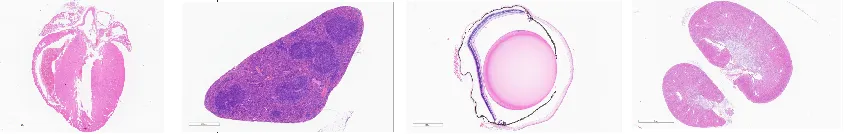

收藏组织学是病理学的基础,病理学研究疾病状态中机体宏观与微观的结构变化,必须以正常机体的组织结构作为参照。组织学技术种类繁多,包括光镜技术、电镜技术、组织化学技术、图像分析技术、细胞培养技术和组织工程,每一类技术又含许多分支技术,有的操作程序十分复杂,有的所用仪器极其精密,其原理涉及物理、化学、生物化学、免疫学、分子生物学等学科的知识。在组织学的光镜技术中,石蜡切片技术是经典而最常用的技术。

石蜡切片的制作流程是固定、取材、脱水透明、包埋、切片、摊片烤片。通过将制备好的石蜡切片进行不同的染色可以清晰地观察到组织的形态结构。染色完成的石蜡切片可保存较长时间,方便后续进行观察。

百奥赛图病理平台拥有专业技术团队,以及完善的硬件设施,可支持不同部位组织石蜡切片的制备,染色。

石蜡切片的应用

烘片完成后的石蜡白片,可根据实验需求进行如下所示不同的染色,然后根据染色方法要求进行水性或者油性封片。

01.H&E染色